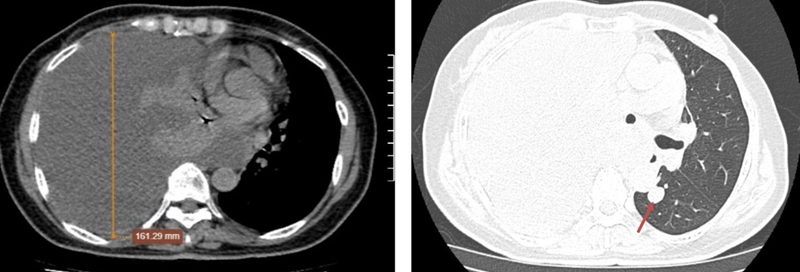

Chụp CT phổi cho thấy hình ảnh tràn dịch màng phổi phải mức độ nhiều, đè ép xẹp hoàn toàn nhu mô phổi, đẩy tim và trung thất lệch trái. Nốt đặc phổi trái phân thùy S6 sát trung thất kích thước 10x15mm, bờ đều, ranh giới rõ, bên trong có tỷ trọng vôi (103 HU) (phân loại Lung RADS 4X – nghi ngờ ác tính cao).

Hình ảnh tràn dịch khoang màng phổi phải mức độ nhiều và nốt đặc phổi trái phân thùy S6 sát trung thất